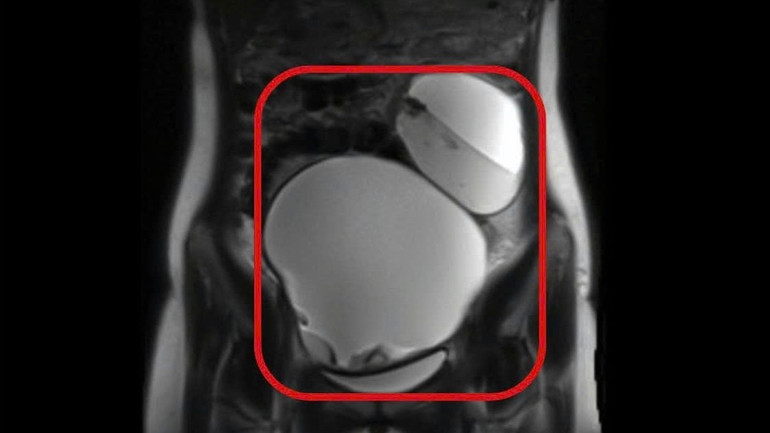

Bệnh nhân N. 17 tuổi, nhập viện ngày 19/12/2025 trong tình trạng đau dữ dội vùng hạ vị. Qua thăm khám, các bác sĩ Bệnh viện đa khoa Thủ Đức phát hiện khối căng lớn vùng bụng dưới kèm biểu hiện đau rõ khi sờ chạm vào. Kết quả chẩn đoán hình ảnh cho thấy hai buồng trứng đều có khối u kích thước lớn chứa dịch, mỡ và vôi hóa.

Hình ảnh chụp vị trí hai khối u.